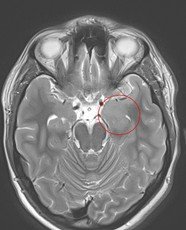

Pentru pacienți, aceste episoade sunt adesea greu de înțeles și pot fi însoțite de teamă și incertitudine. Investigațiile imagistice au adus însă explicația: RMN-ul cerebral a evidențiat o mică tumoră profundă, situată pe fața internă a lobului temporal stâng, la nivelul hipocampului și al nucleului amigdalian.

Deși tumora era relativ mică – aproximativ doi centimetri – localizarea ei era extrem de delicată. Hipocampul este una dintre structurile centrale ale creierului, implicată în memorie și procesarea emoțiilor, iar lobul temporal stâng joacă un rol important în limbaj.